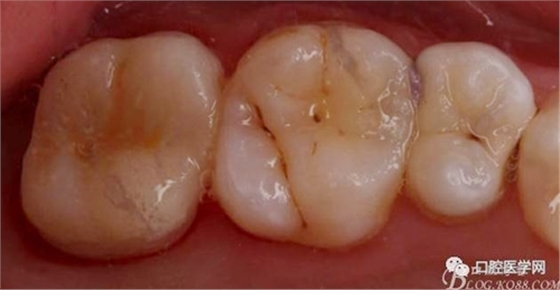

口內(nèi)粘接完成,幾乎無(wú)調(diào)整,就位完全,咬合良好

口內(nèi)檢查咬合,情況良好。